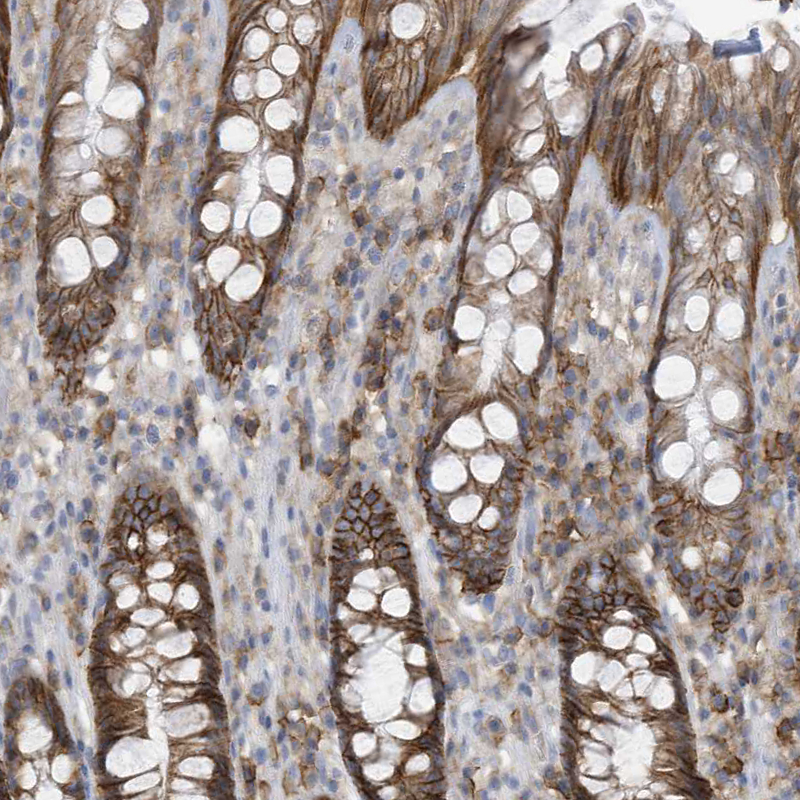

Immunohistochemistry analysis in human prostate and skeletal muscle tissues using HPA035240 antibody. Corresponding SLC1A5 RNA-seq data are presented for the same tissues.